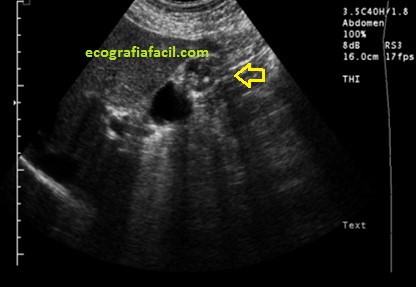

Finalmente, atentos siempre a situaciones de semiología anómala, no conocida o extraña como la de la imagen 6, donde podemos ver afectación tumoral de la vesícula y donde vemos signos ecográficos muy llamativos, como puede ser la heterogenicidad y la deformidad de la ecoestructura, donde vemos como el fundus vesicular se ve desesctruturado, como con microcalcificaciones y áreas de mala transmisión de sonido…la otra parte de la vesícula anecoica, normal.